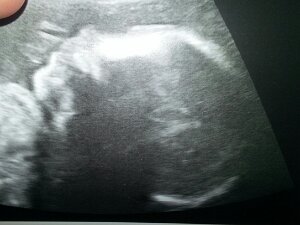

Cordie

October 15th